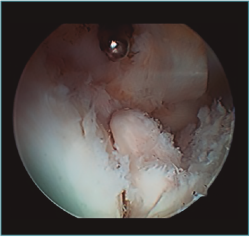

Cirugía artroscópica

La artroplastia osteocapsular artroscópica persigue los mismos objetivos que la cirugía abierta, con una serie de ventajas como son la menor incisión, la menor agresión para las partes blandas, la disminución del sangrado intraoperatorio y la mayor precisión en el fresado y recontorneado óseo, al contar con la magnificación proporcionada por la óptica, así como el mejor control del dolor del paciente en el postoperatorio y el comienzo precoz de la rehabilitación. Sin embargo, es un procedimiento demandante técnicamente que exige tener una amplia experiencia previa con procedimientos más simples. Los factores que aumentan la complejidad del procedimiento con respecto a otro tipo de artroscopias del codo son, dejando aparte los relacionados con la causa que desencadenó la rigidez, que ya fueron mencionados: el volumen articular reducido, la escasa distensibilidad de la cápsula engrosada y la presencia de cicatrices intraarticulares e hipertrofia sinovial, que dificultan de manera importante la visualización y el trabajo articular que tenemos que hacer. Esto, sumado a la restricción de 2 horas de isquemia como máximo de las que disponemos, puede poner en jaque a cirujanos inexpertos que tengan que terminar el procedimiento sin haber conseguido concluir los objetivos del tratamiento (Figura 7).

Figura 7. Sinovitis exuberante que no deja ver la articulación radiocapitelar desde el portal anteromedial proximal, en una artritis postraumática con volumen articular reducido.